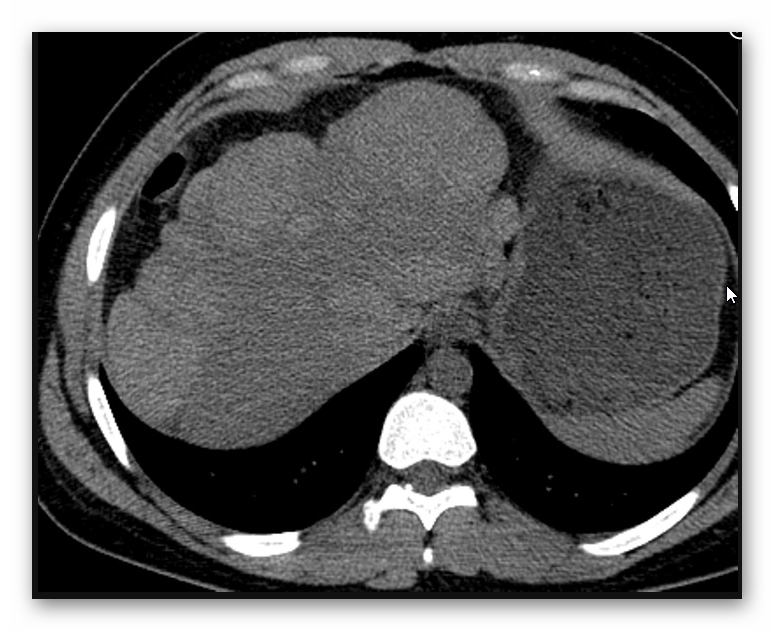

MARSKOŚĆ WĄTROBY

TK